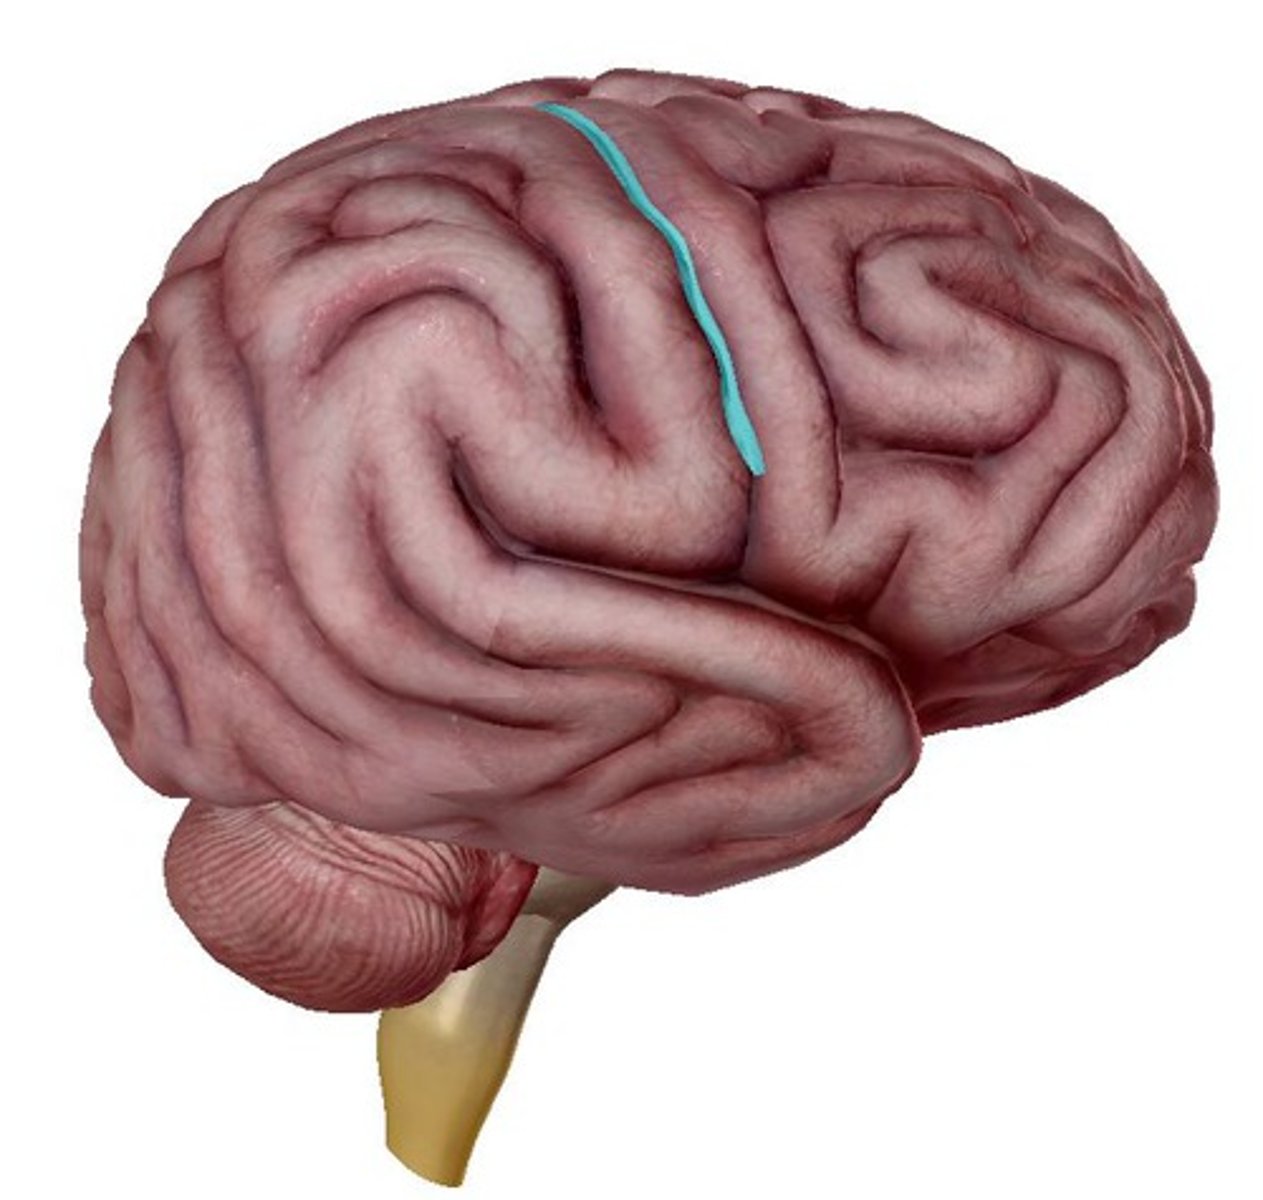

central sulcus

precentral gyrus

postcentral gyrus